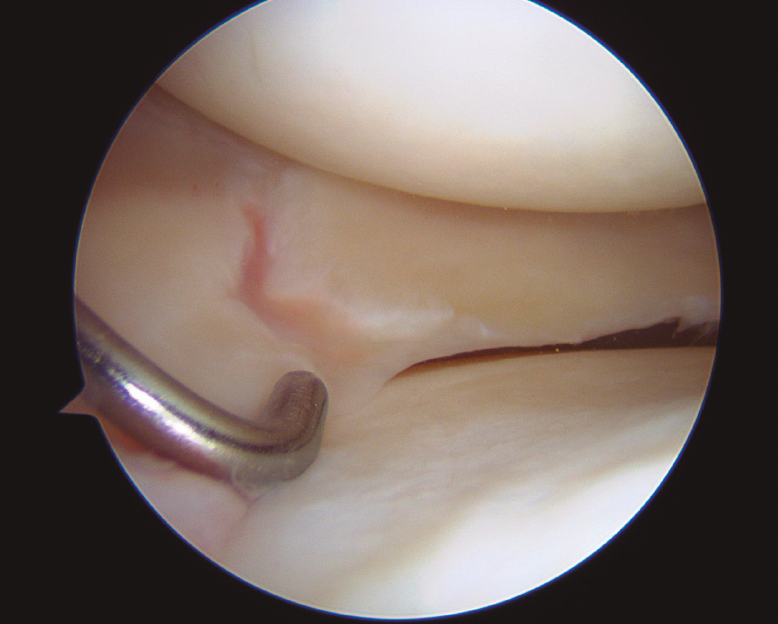

Rotura radial cicatrizada de menisco externo

Healed radial tear of lateral meniscus

Durante la cirugía para realizar una plastia del ligamento cruzado anterior en un paciente de 19 años, la exploración de la rodilla descubrió la presencia de una rotura radial cicatrizada del menisco externo, que se comprobó estable a la palpación.